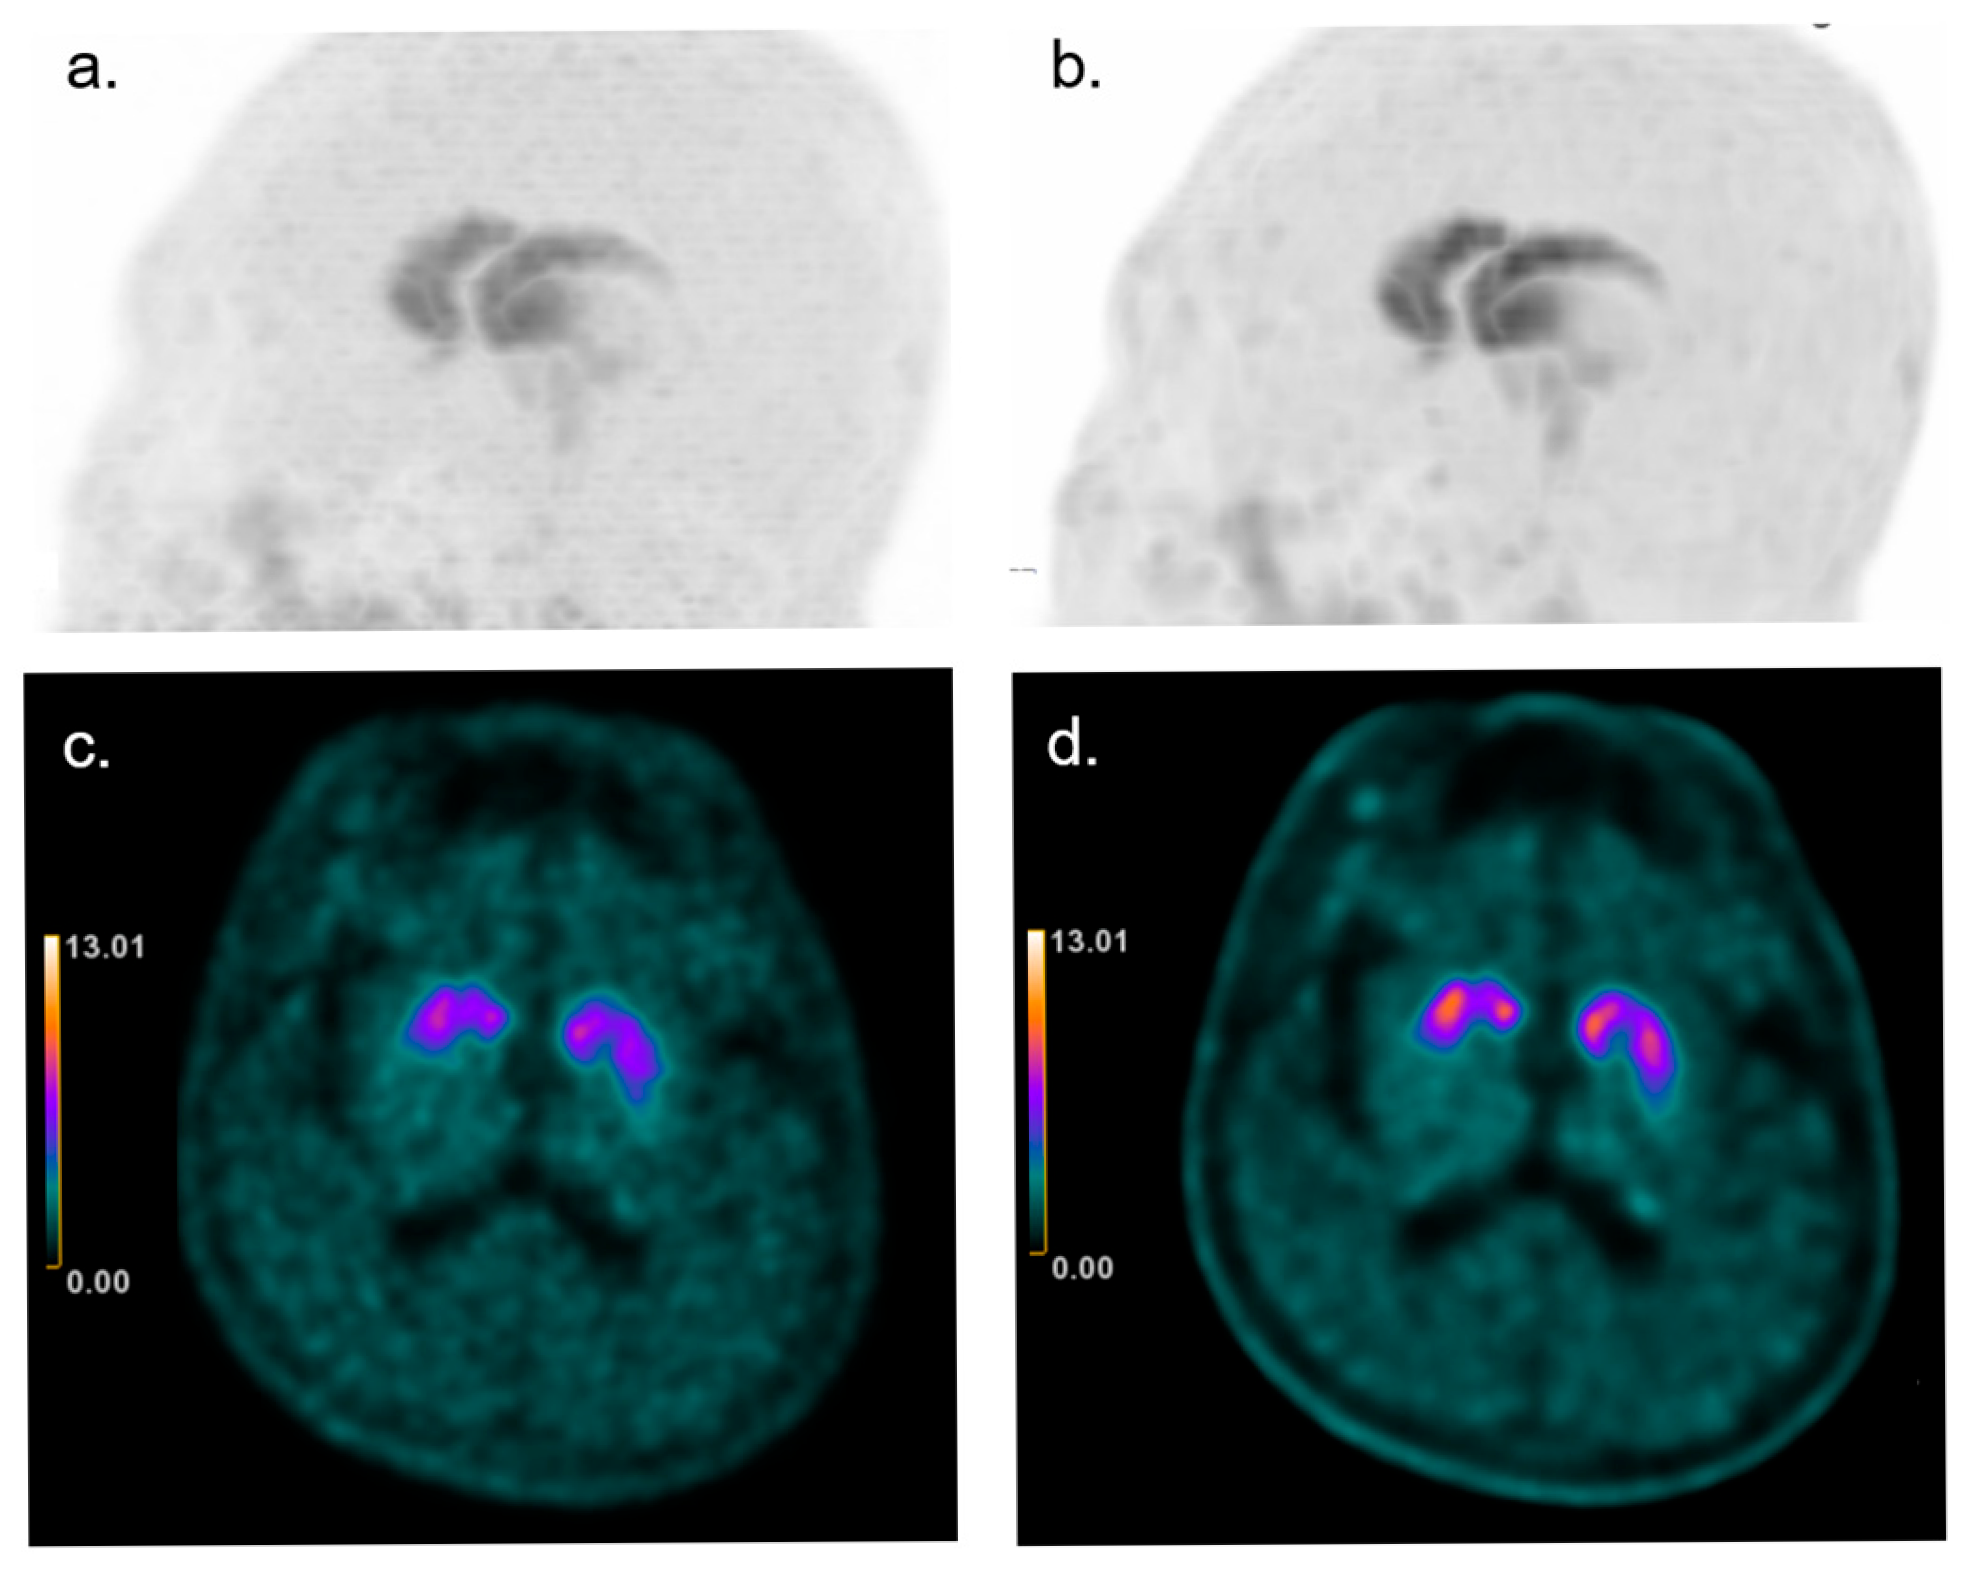

3.6. Effect on Visual Interpretation